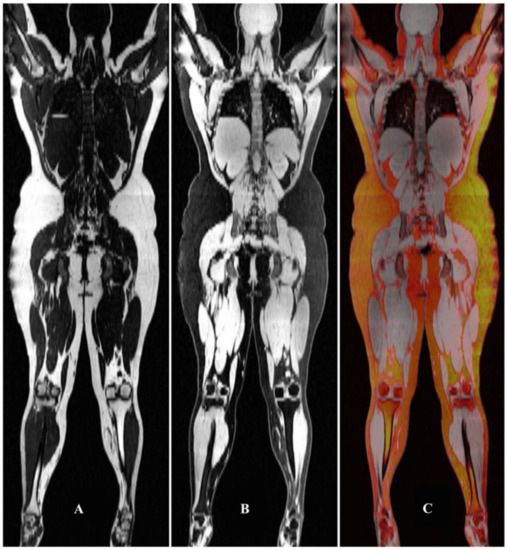

3.4. MRI for Structural Evaluation: Simultaneous Evaluation of Multiple Tissues by MRI